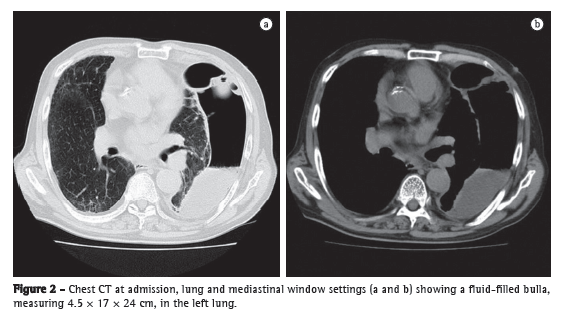

A 79-year-old man sought treatment in the emergency room, complaining of a 3-month history of persistent fever, chest pain, and general fatigue. He had a smoking history of 60 pack-years and had been a heavy drinker of Japanese sake (180 mL/day) for the past thirty years. Laboratory test results indicated severe inflammation, and a chest X-ray showed a giant bulla with a diameter of 24 cm in the left lung (Figure 1a). By his own account, he had no history of abnormalities on X-rays, and his latest medical check-up, conducted in the preceding year, had produced no abnormal findings (Figure 1b). CT scans of the chest revealed that the bulla was fluid-filled and measured 4.5 × 17 × 24 cm (Figure 2). The patient was diagnosed as having a lung abscess and was admitted to our hospital.